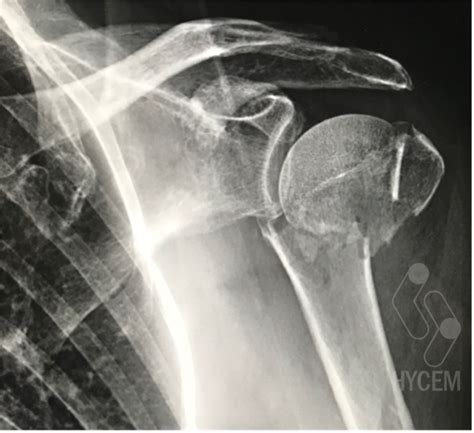

Ante una caída o un golpe que resulte en dolor y limitación funcional en el brazo, es crucial buscar atención médica inmediata. Los datos del caso se obtienen a través de la entrevista clínica, exploración física y la historia clínica. En radiografías de la articulación glenohumeral se observa la fractura.

Una paciente acudió al servicio de urgencias tras una caída en domicilio. Tras la valoración, se observó una fractura proximal de cabeza del húmero izquierdo. Se realizaron pruebas complementarias como ECG, analítica de sangre y radiografía de tórax, las cuales resultaron normales.

- Reemplazo parcial o total de la cabeza del húmero (artroplastia): Se considera cuando la fractura afecta gravemente la cabeza del húmero, especialmente en pacientes con osteoporosis avanzada. La artroplastia total inversa de hombro se ha mostrado como una opción válida en fracturas complejas en pacientes mayores de 65 años.